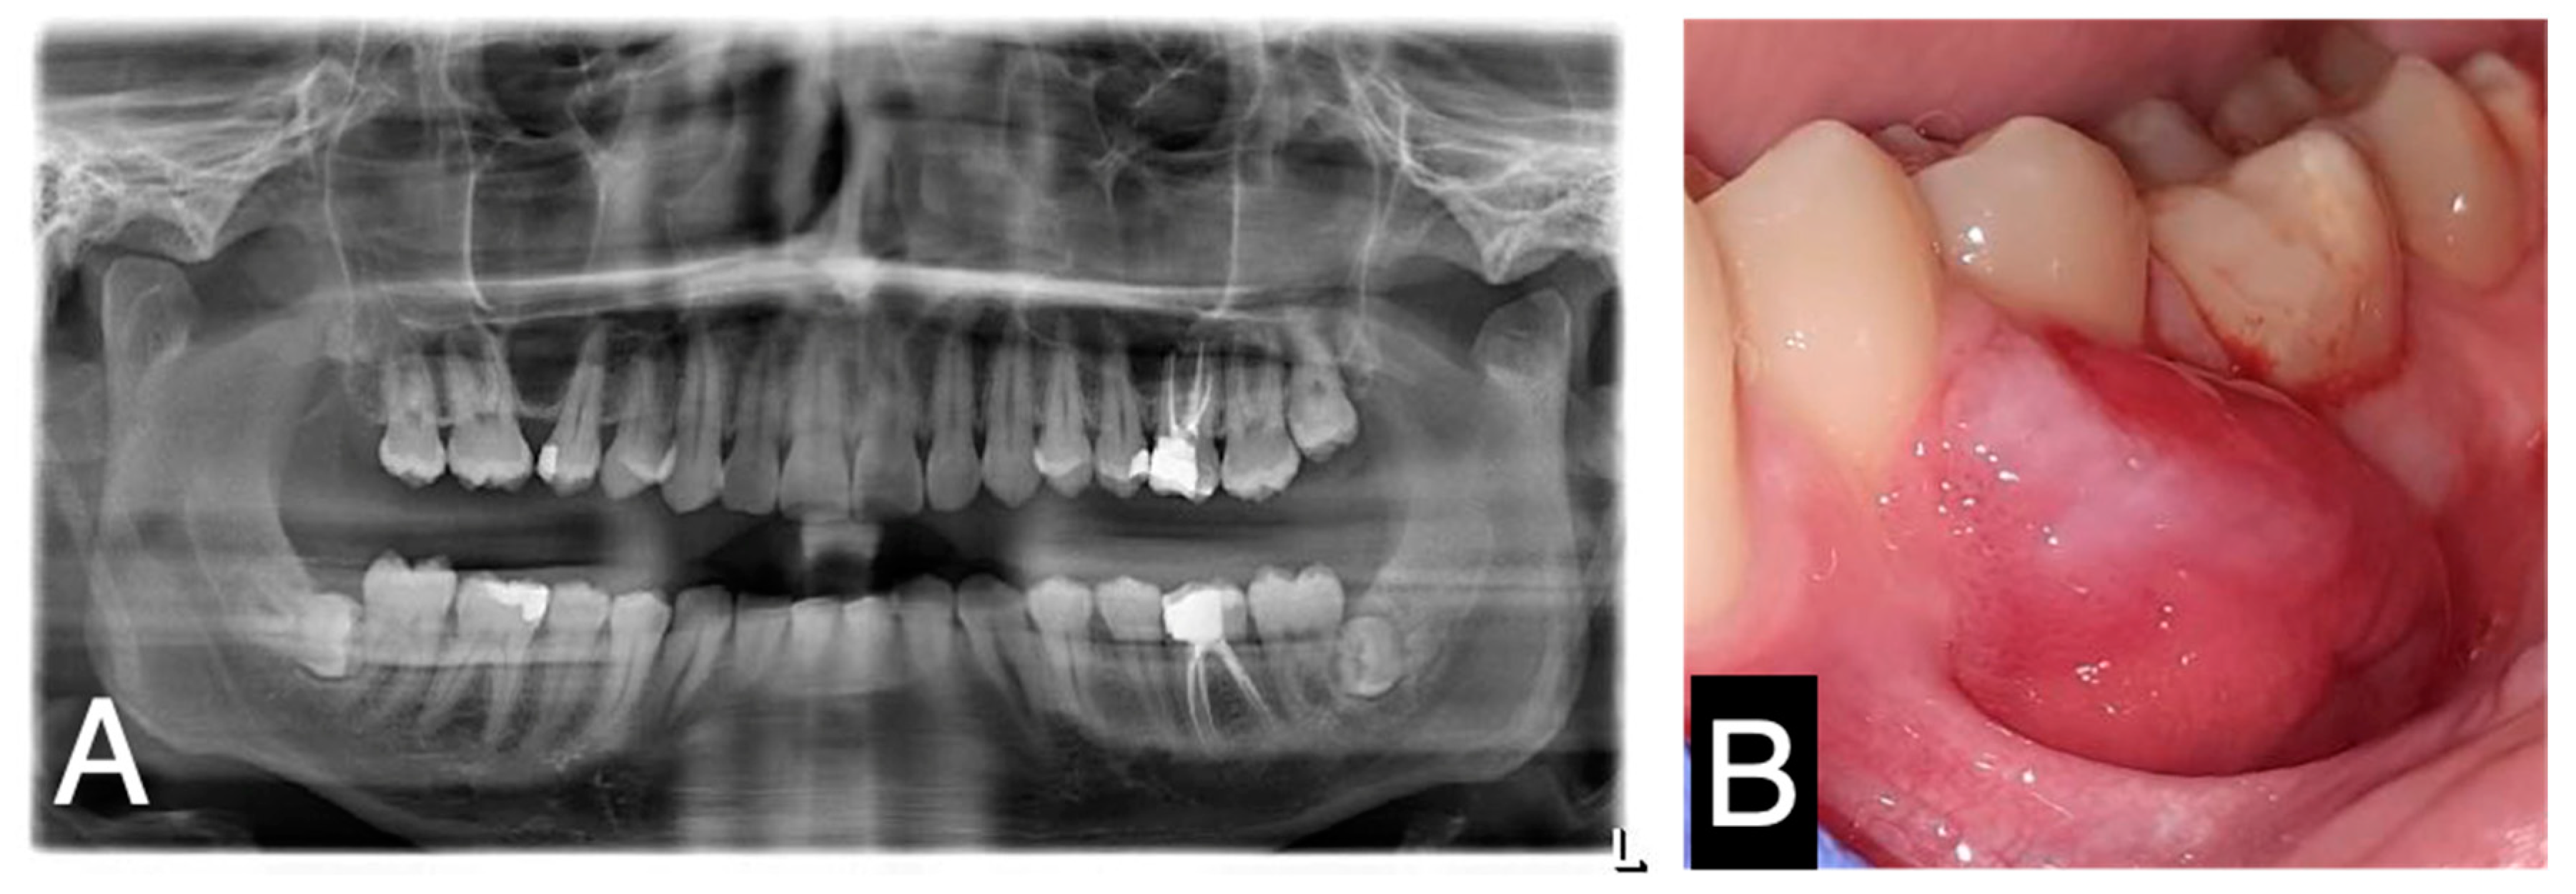

2. Case Report